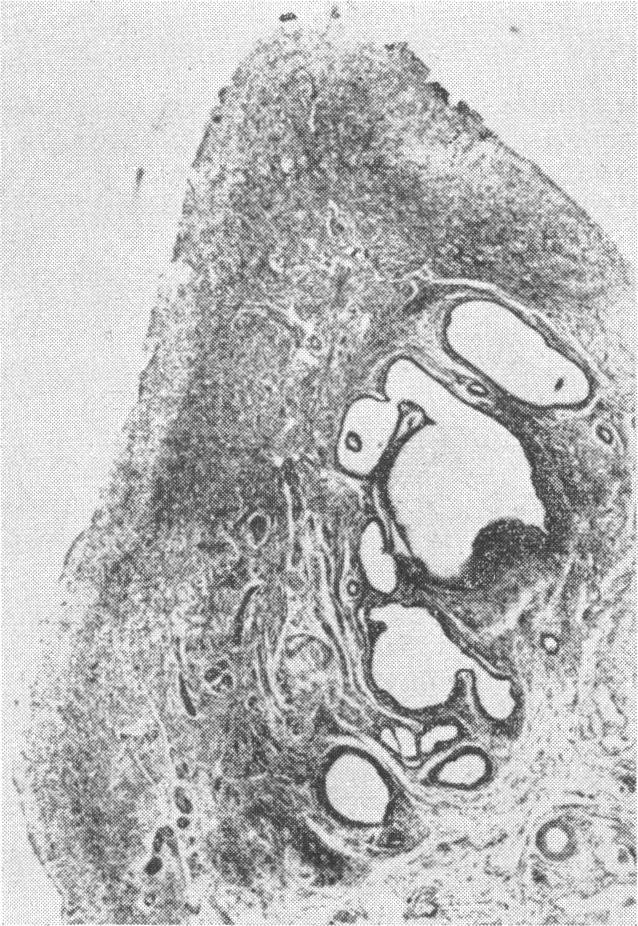

Ovarian pathology in primary amenorrhoea.

Proc R Soc Med. 1970 Mar;63(3):294-7. doi: 10.1177/003591577006300337.